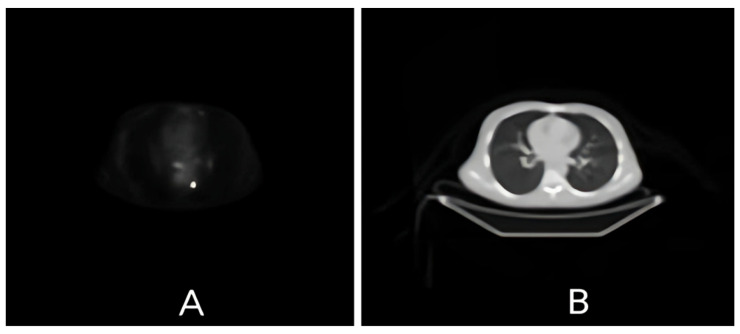

背景/目的:多模态图像配准在现代医学成像中起着至关重要的作用,它使正电子发射断层扫描(PET)和计算机断层扫描(CT)等互补模式得以整合。本研究比较了三种广泛使用的图像配准技术——使用模态变换的恶魔图像配准、使用医学图像配准工具箱(MIRT)的自由形式变形和MATLAB基于强度的配准——在改善PET/CT图像对齐方面的性能。方法:对临床扫描得到的100张匹配的PET/CT图像切片进行分析。预处理技术,包括直方图均衡化和对比度增强(通过imadjust和adapthisteq),被应用于最小化强度差异。每种配准方法在sigma流体(范围4-8)、直方图箱(100至256)和插值方法(线性和三次)的不同参数条件下进行评估。使用定量指标评估性能:均方根误差(RMSE)、均方误差(MSE)、平均绝对误差(MAE)、Pearson相关系数(PCC)和标准差(STD)。结果:在sigma流体值为6时,Demons配准达到最佳性能,RMSE为0.1529,显示出优越的计算效率。MIRT对复杂解剖变形具有较好的适应性,RMSE为0.1725。当结合对比度增强时,MATLAB基于强度的配准产生了最高的精度(在alpha = 6时RMSE = 0.1317)。预处理提高了配准精度,将RMSE降低了16%。结论:每种配准技术都有其独特的优势:Demons算法适用于时间敏感型任务,MIRT适用于精度驱动型应用,基于matlab的方法可灵活处理大型数据集。本研究为在研究和临床环境中优化PET/CT图像配准提供了一个基础框架。

Background/Objective: Multimodal image registration plays a critical role in modern medical imaging, enabling the integration of complementary modalities such as positron emission tomography (PET) and computed tomography (CT). This study compares the performance of three widely used image registration techniques-Demons Image Registration with Modality Transformation, Free-Form Deformation using the Medical Image Registration Toolbox (MIRT), and MATLAB Intensity-Based Registration-in terms of improving PET/CT image alignment. Methods: A total of 100 matched PET/CT image slices from a clinical scanner were analysed. Preprocessing techniques, including histogram equalisation and contrast enhancement (via imadjust and adapthisteq), were applied to minimise intensity discrepancies. Each registration method was evaluated under varying parameter conditions with regard to sigma fluid (range 4-8), histogram bins (100 to 256), and interpolation methods (linear and cubic). Performance was assessed using quantitative metrics: root mean square error (RMSE), mean squared error (MSE), mean absolute error (MAE), the Pearson correlation coefficient (PCC), and standard deviation (STD). Results: Demons registration achieved optimal performance at a sigma fluid value of 6, with an RMSE of 0.1529, and demonstrated superior computational efficiency. The MIRT showed better adaptability to complex anatomical deformations, with an RMSE of 0.1725. MATLAB Intensity-Based Registration, when combined with contrast enhancement, yielded the highest accuracy (RMSE = 0.1317 at alpha = 6). Preprocessing improved registration accuracy, reducing the RMSE by up to 16%. Conclusions: Each registration technique has distinct advantages: the Demons algorithm is ideal for time-sensitive tasks, the MIRT is suited to precision-driven applications, and MATLAB-based methods offer flexible processing for large datasets. This study provides a foundational framework for optimising PET/CT image registration in both research and clinical environments.